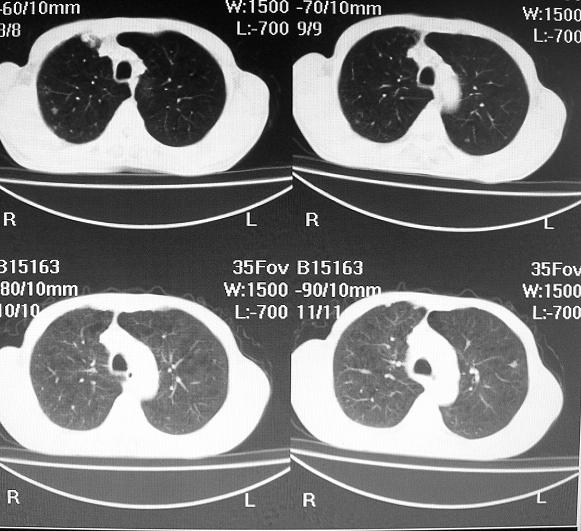

标题: CT10688:男63岁胸痛来诊

男63岁胸痛来诊

右肺病灶前缘不平整,略呈分叶状,其后方胸膜下脂线消失且似有向胸壁浸犯,左下肺球形灶内可见不规则空洞影,余双肺内可见多枚结节影,结合病史支持考虑肺癌肺内转移胸膜转移,便双肺后部病灶倒也是结核好发区域,建议穿刺活检

右下肺周围性肺ca并双肺及右侧胸膜转移。[emb6]

右下肺周围性肺ca并双肺及右侧胸膜转移。支持

右下肺周围性肺ca并双肺及右侧胸膜转移。

右下肺周围性肺ca并双肺及右侧胸膜转移。单看病变像炎性假瘤。

右下肺癌,双肺及胸膜转移

右下肺癌伴双肺及胸膜转移。

左肺病灶内可见空泡征及典型的胸膜牵拉征,不排除原发周围型肺癌的可能.